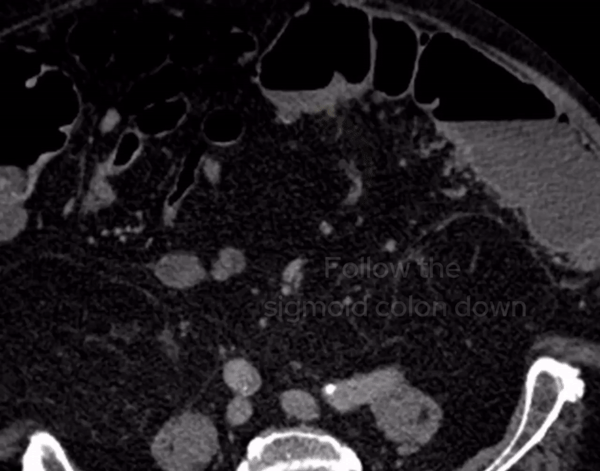

If we look at a lateral STIR sequence of the lumbar spine, we can see high signal in the lateral aspect of the L3-4 disc which is continuous with the abscess formation within the right psoas. This highly suggests a spondylodiscitis as the primary pathology leading to secondary psoas abscess.

When we scroll through this sagittal STIR sequence of the lumbar spine we will see high signal within the L3-4 disc adjacent to the right psoas abnormality.